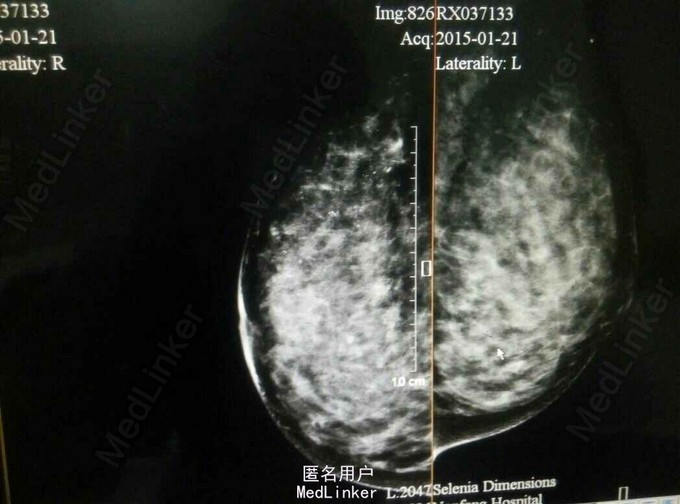

查体:右乳头糜烂,伴透明渗液,局部皮肤红肿,双乳未触及明显肿物 辅助检查:如下,钼靶可见右乳局部可见散在分布细小多形性钙化,彩超可见一细小不规则区域

诊断:右乳癌?? 治疗:右乳头取材行细胞学检查,发现有肿瘤细胞存在,于是行右乳钙化灶切取活检术,送病理证实为右乳Paget's病伴局部高级别导管内癌,ER(-)、PR(-)、HER-2(3+)、Ki-67(+,30%),于是行右乳癌改良根治术+I期假体植入术,术后行EC*4-T*4方案化疗